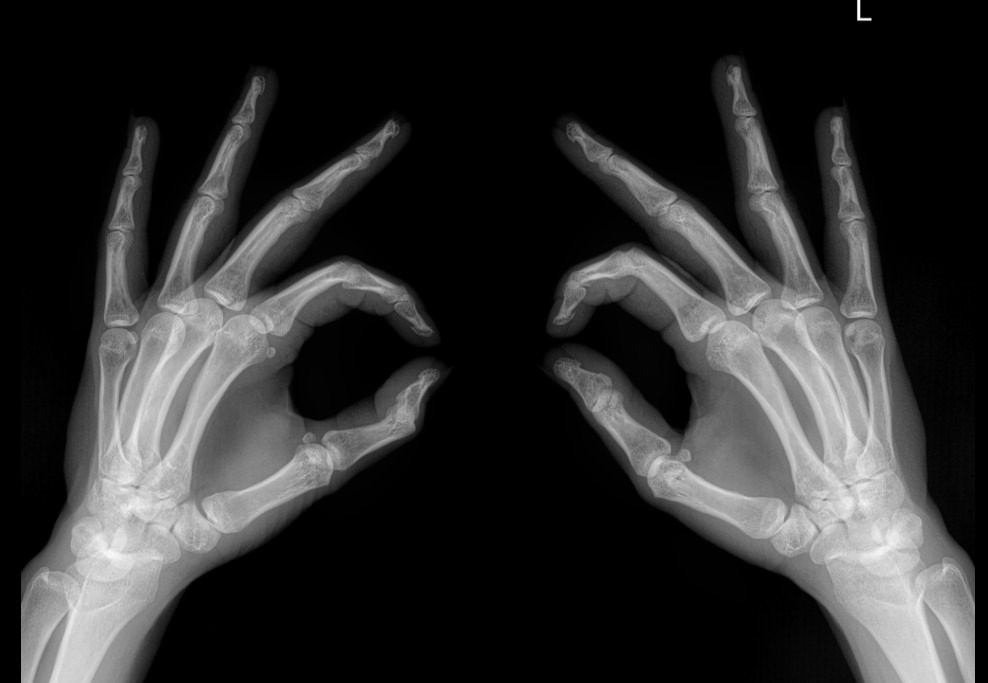

Диагностику выполняют без подготовки. Пациент закатывает рукава, снимает с рук все украшения, надевает защитный фартук и садится к снимочному столу. Руки на пластину детектора обычно кладут ладонями вниз и разводят пальцы, локти тоже лежат на столе. Существует и косая укладка, когда кисти кладут боком, но указания для этого должны быть в направлении.

На момент съемки, занимающей 1-2 секунды, необходимо замереть и не шевелить руками. Описание снимка можно получить в этот же день.